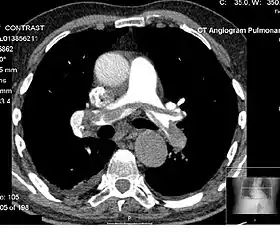

Angiography

Computed tomography angiography (CTA) is a type of contrast CT to visualize the arteries and veins throughout the body.[47] This ranges from arteries serving the brain to those bringing blood to the lungs, kidneys, arms and legs. An example of this type of exam is CT pulmonary angiogram (CTPA) used to diagnose pulmonary embolism (PE). It employs computed tomography and an iodine-based contrast agent to obtain an image of the pulmonary arteries.[48][49][50]